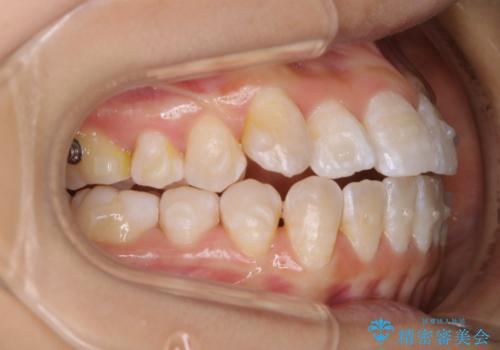

前歯のがたつきとオープンバイト:インビザラインでまとめて治す

- 噛み合わせと、前歯のがたつきが気になるとご相談にいらした方です。インビザラインFULLで綺麗な歯並びと噛み合わせを作ることが出来ました。

オープンバイトの方への治療は、通常抜歯を行いワイヤーによる矯正治療を行うことが多いですが、今回はインビザラインの特性を生かし、非抜歯にて綺麗な歯並びを作ることが出来ました。